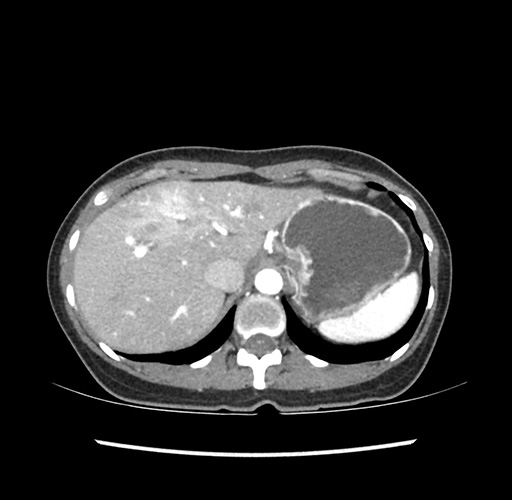

Imaging Analysis

Look through the patient's CT scan to identify any areas of concern for the necessary procedure.

Based on your CT findings, which issue(s) would give reason for "planned slowing down moment(s)" in this case?

Considering a standard left lateral sectionectomy procedure, what step(s) of the operation would you do differently in this case ?